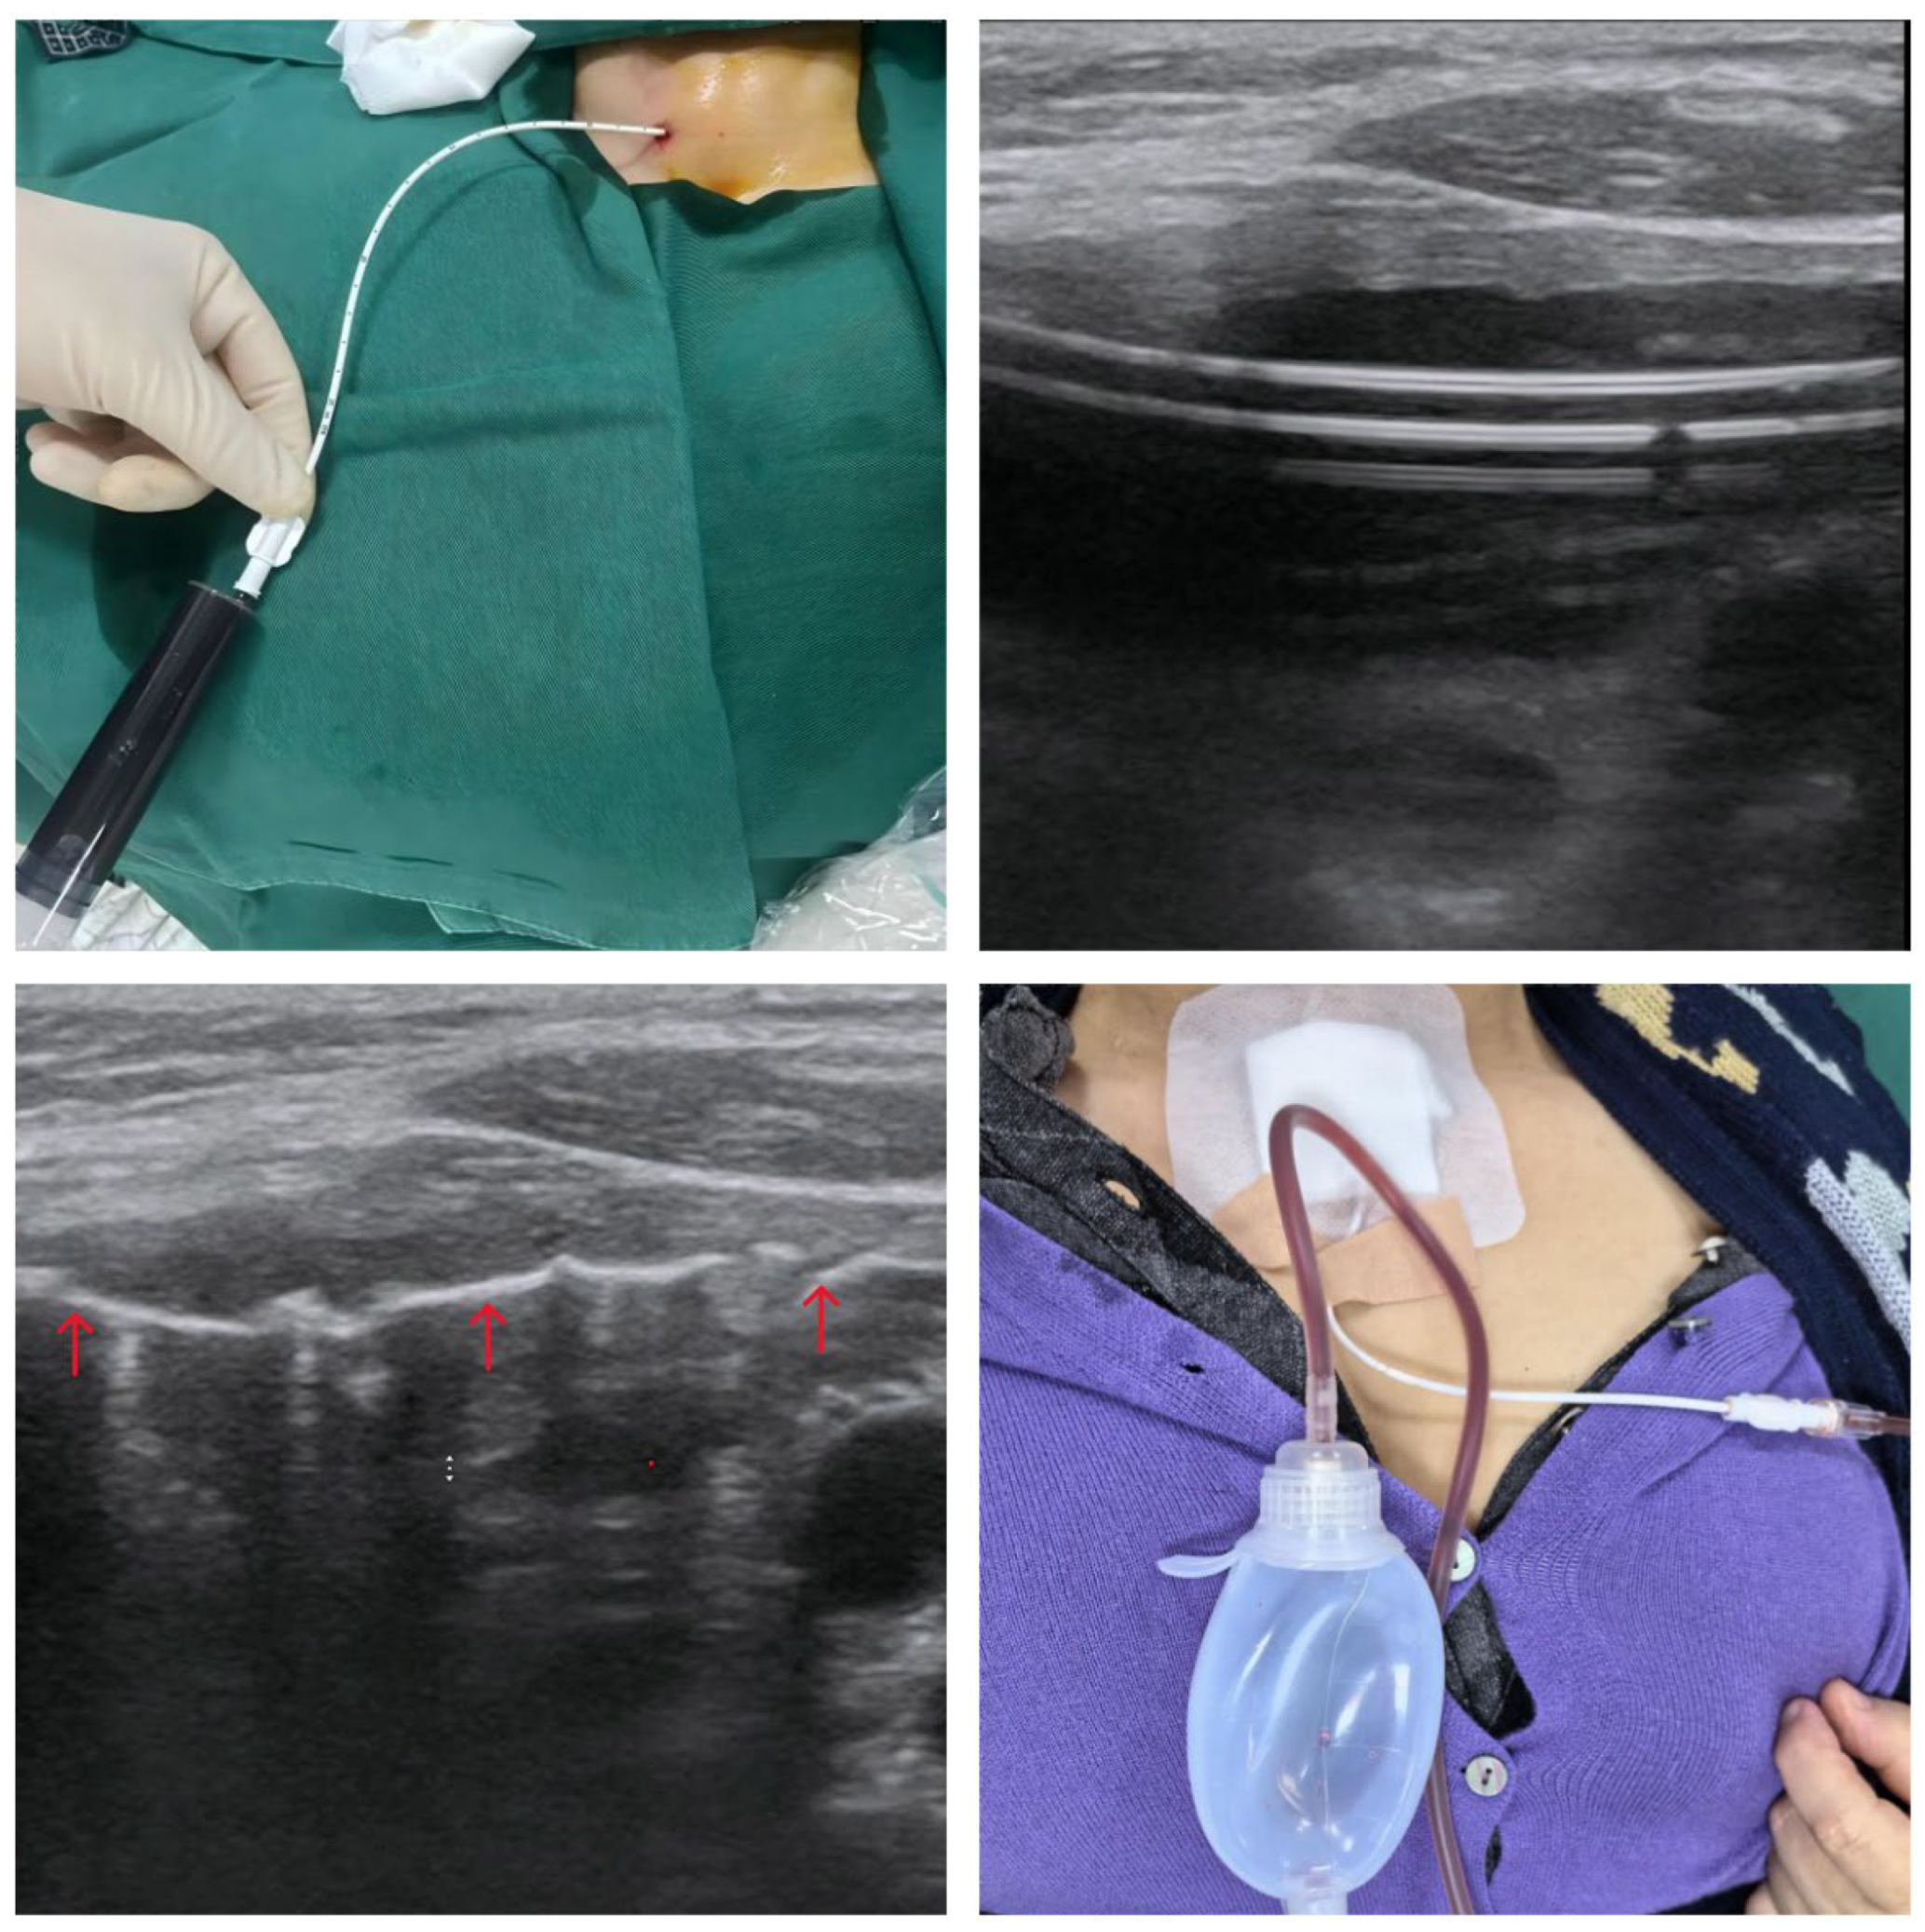

• Catheter Placement: Under continuous real-time US guidance, a point of entry was selected on the anterior neck medial to the sternocleidomastoid muscle. After local infiltration with 2% lidocaine, a small 2 mm skin incision was made. A modified trocar system containing a soft, 7-French catheter with multiple side holes was advanced percutaneously into the center of the cyst cavity. The selection of a soft, atraumatic catheter over a rigid metal needle was a deliberate technical choice to minimize the risk of traumatizing the delicate and vascular cyst wall during fluid aspiration and subsequent cyst collapse, thereby reducing the likelihood of iatrogenic hemorrhage.

• Aspiration and Lavage: Once the catheter's position within the cyst was confirmed by US, the inner stylet was removed. The catheter was then connected to a 20 mL syringe, and a total of 100 mL of dark fluid was aspirated (Figure 2A). A sample of the fluid was sent for cytological analysis, which subsequently confirmed the presence of benign follicular cells and hemosiderin-laden macrophages, with no evidence of malignancy. Following complete aspiration, the cyst cavity was repeatedly lavaged with sterile saline until the aspirated fluid became clear. This step was deemed crucial for removing hemorrhagic debris and residual proteinaceous material that could potentially dilute the sclerosant and inhibit its efficacy.Following this, ultrasound could clearly observe the side-hole catheter positioned within the residual cavity(Figure 2B); this is safer than a metal needle. This is because a metal needle tip risks accidentally puncturing normal tissue, causing re-bleeding, or its tip may become displaced, preventing re-entry into the cavity and leading to risks associated with the drug injection.

• Sclerotherapy: A sclerosant foam was prepared using the Tessari method by vigorously mixing 4 mL of 3% polidocanol solution with 24 mL of room air between two syringes connected by a three-way stopcock. The resulting microfoam was then slowly injected into the completely collapsed cyst cavity via the indwelling catheter. Real-time US imaging confirmed the uniform distribution of the hyperechoic foam throughout the cavity, ensuring complete and intimate contact with the entire surface area of the secretory epithelial lining (Figure 2C).

• Prolonged Drainage: After the sclerosant injection, the catheter was secured to the skin with a suture and a sterile dressing. The distal end of the catheter was capped and sealed for the initial 24 hours. This dwell time was intended to maximize the contact period between the polidocanol and the cyst wall to ensure complete chemical ablation. After 24 hours, the catheter was connected to a portable negative pressure drainage bottle to facilitate continuous, active drainage of post-procedural fluid (Figure 2D).

Figure 2. Procedural Details. (A) Aspiration of 100 mL of dark, hemorrhagic fluid via the indwelling catheter. (B) Ultrasound image showing the soft catheter (hyperechoic "tram-track" sign) within the collapsed cavity after aspiration. (C) Ultrasound image during sclerotherapy, showing hyperechoic polidocanol foam (red arrow) filling the residual cavity. (D) 24 hours after polidocanol injection, the catheter is connected to a negative pressure drainage bottle for continuous drainage of light-colored inflammatory exudate.